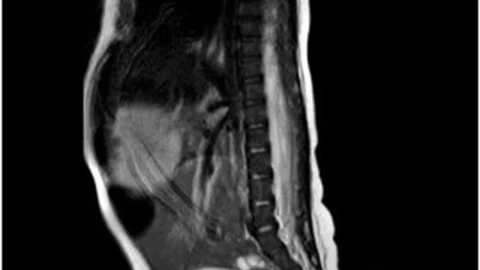

De acuerdo a los médicos, la cola del bebé tiene conexión con los nervios del cuerpo, esto lo confirmaron después de que procedieron a pellizcarla con una aguja, lo que provocará el llanto del bebé.

La cola tiene una medida de 5.7 cm de longitud y de entre 3 y 5 milímetros (mm) de diámetro, además de que se encuentra ubicada en la hendidura interglútea.

Finalmente señalaron que la cola de la bebé está cubierta de piel y tiene un poco de pelo fino, poco visible, pero esta no tenía movimiento alguno.

Los médicos lograron retirar su cola a la bebé cuando tenía dos meses y siguieron estudiando su extremidad. Al cabo de dos meses, la cola fue revaluada, encontrando que su extremidad adicional había crecido 0.8 centímetros, por lo que fue extirpada y la zona afectada reconstruida.